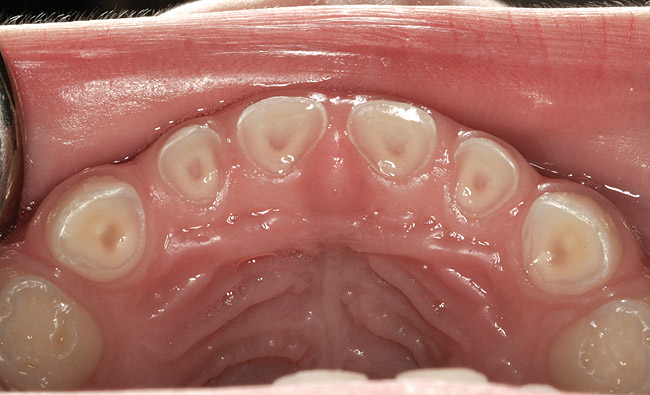

The pattern for bone growth resides not in the bone itself but rather in the soft tissue and muscle that encase the bone.42 Oral-facial muscle tone and tongue tonicity create a framework for normal development of the nasomaxillary complex and mandible.43 SDB is noted in children with pathologic hypotonia of facial and tongue muscles. Children born with a normal palate and oral-facial hypotonia will develop a high, narrow palate over the first year of life (Figure 3 and Figure 4). Children born with a high, narrow palate have hypotonia at birth. These myofunctional changes may be detected in utero.43

(10.) Narrow maxilla with tooth wear and bilateral crossbite.

Figure 10